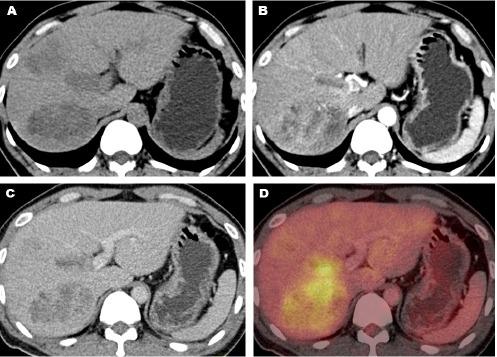

Two patients with previously untreated HCC and 7 cases with previously treated HCC had FDG-avid PVTT in contrast-enhanced FDG PET/CT scan. During the arterial phase of CT scan, portal vein thrombus showed contrast enhancement in 8 out of 9 patients (88.9%). PET scan showed an increased linear FDG uptake along the thrombosed portal vein in all patients. The mean greatest diameter of thrombosed portal veins was 1.8 ± 0.2 cm, which was significantly greater than that observed in normal portal veins (P<0.001). FDG uptake level in portal vein thrombus was significantly higher than that of blood pool in the reference normal portal vein (P=0.001). PVTT was caused by the direct extension of liver tumors. All patients had visible FDG-avid liver tumors in contrast-enhanced images. Five out of 9 patients (55.6%) had no extrahepatic metastasis, 3 cases (33.3%) had metastasis of regional lymph nodes, and 1 case (11.1%) presented with distant metastasis. The median estimated survival time of patients was 5 months.

The intraluminal filling defect consistent with thrombous within the portal vein, expansion of the involved portal vein, contrast enhancement, and linear increased FDG uptake of the thrombus extended from liver tumor are findings of FDG-avid PVTT from HCC in contrast-enhanced FDG PET/CT.